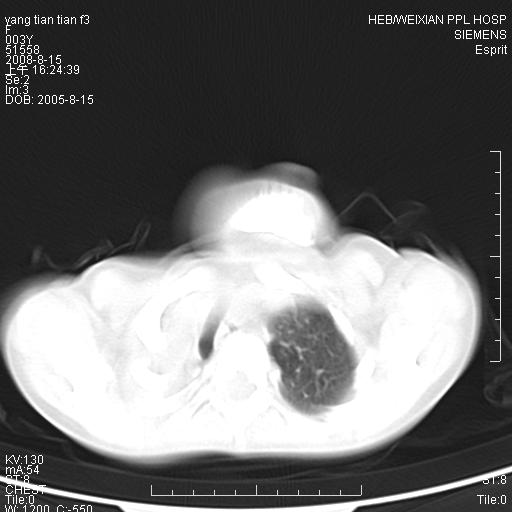

患儿,女,5岁,平素活动后气短,左侧面瘫.右侧胸廓较左侧塌陷.

两侧胸廓不甚对称,左侧稍膨隆,右肺体积明显变小,密度增高,未见正常通气肺组织,纵隔结构明显右移,心脏边缘欠清,外形似增大。纵隔血管间隙不清晰,左肺外形增大,部分肺组织突向右侧胸腔,左肺内未见异常密度影,右侧支气管逐渐变细,其内未见异常密度影。右侧未见叶及段支气管。右侧膈肌升高。

1。右肺体积小(考虑右肺发育不全)

2。左肺代偿性增大

3。心影增大?